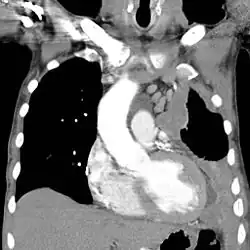

![]() | |

| CT scan showing a left sided mesothelioma with an enlarged mediastinal lymph node | |